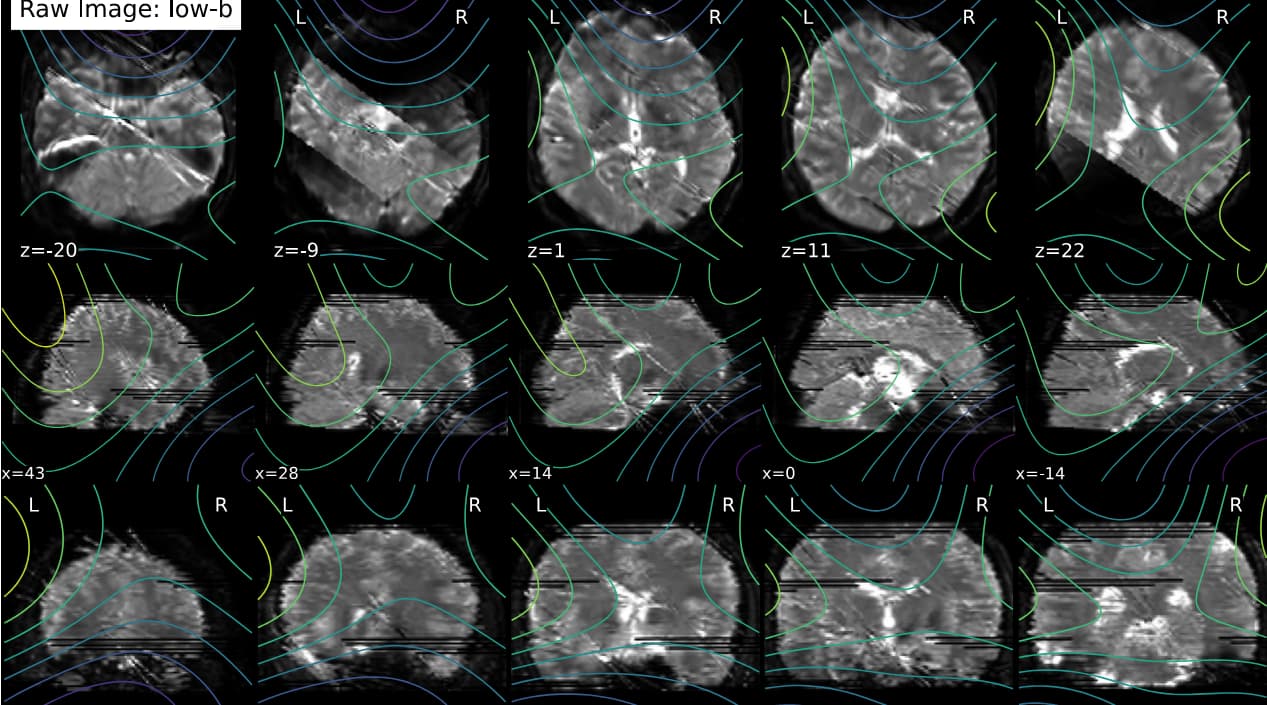

I’m using QSIprep 0.22.0 for preprocessing a dMRI dataset. For two subjects, the preprocessed data seem stripped -but not as the whole slices are missing- evident as early as in the denoising report:

The raw data has no evident issues. I repeated the analysis with QSIprep 1.0.2; the issue remained, but different slices were missing.